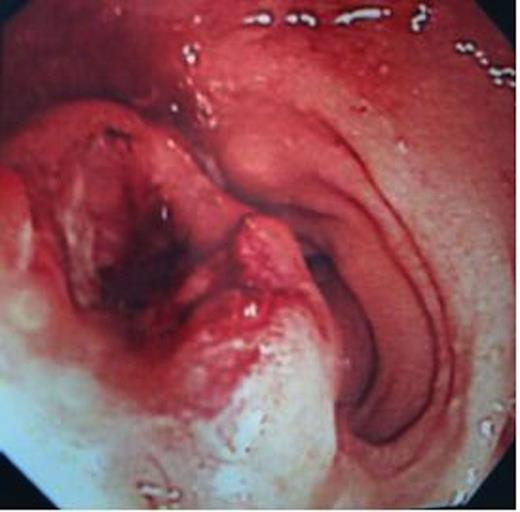

She underwent colonoscopy, which revealed a fungating tumour at 10 cm from the anal verge in the rectum and rest of the colon was normal (Figure 1). The histopathological examination of the biopsy revealed a poorly differentiated invasive adenocarcinoma (Figure 2).

On endoscopy, the colo-rectal metastasis appear as diffuse thickening of the colonic wall mimicking linitis plastica or like in crohn’s disease with ulcerated or nodular areas rather than as a solitary, discrete mass seen in primary colonic lesion (1). But the differentiation was made more challenging in our case, as colonoscopy revealed a solitary fungating mass arising from the rectal mucosa mimicking a primary rectal cancer. Histopathological examination by itself may not be conclusive as the tumour invasion is primarily in the sub-serosa, so unless deep endoscopic biopsies are available the diagnosis will be made only after resection of the tumour. But immunohistochemical markers such as ER, PR, gross cystic disease fluid protein (GCDFP-15), and differential expression of CK7 and CK20 can facilitate an accurate diagnosis as seen in the present report.